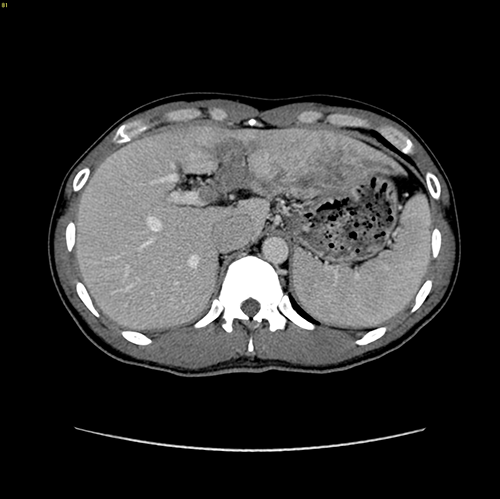

左肝癌并门静脉左支癌栓---左半肝切除